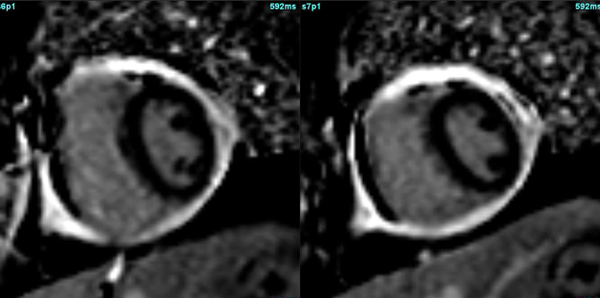

Case 151: 1 or 2 or 3 or 4…Counting the Sinuses and Cusps

Cardiac MRI does not show vegetations, easily especially if small. However, evaluating the transaxials through the valve may help pick up small nodules and to rule out mimics.